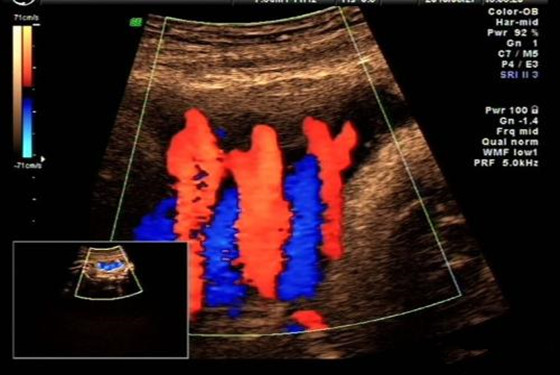

话说胎儿脐带绕颈的现象比较多见,有90%以上的产妇在临产前,会有胎儿脐带绕颈的情况,不过孕妈妈不必太过于担心,即便是脐带绕颈也是可以顺利生产的,一些网友说脐带绕颈80%是男孩,那么,这样的说法有科学依据吗,我们一起来下文中寻找答案。

从古至今,有关胎儿性别的话题层出不穷,有很多网友称,脐带绕颈的80%是男孩,其实,这种说法一点都不科学。胎儿之所以会出现脐带绕颈的现象,那是因为胎儿存活于羊水中,他在子宫腔内可以自由的活动,在活动的过程中出现脐带绕颈的现象也是正常的,一般怀孕6-8个月时,胎儿出现脐带绕颈的可能性比较大,到了孕34周以后,出现脐带绕颈的可能性就比较小了,即便是临产时出现这样的情况,也是可以顺利生产的,这一点孕妈妈不必过于担心,只要做好孕期检查就可以。